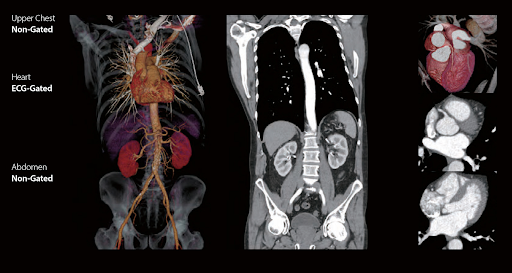

Технология vHP3 позволяет объединять несколько специализированных исследований в рамках одного сканирования.